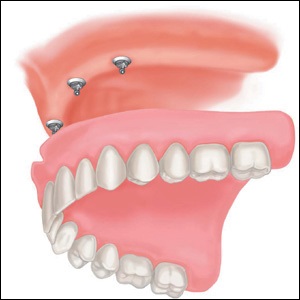

Transgigivalno végez műveletet (a gingiva). A design meg az állcsont helyett az elveszett foggyökér.

Mini implantátumok kellően kis csavar, amelynek méretei 2 mm átmérőjű.

Ez egy darabból álló kialakítás álló az implantátum és a felépítmény. Lapos implantátum titánból vagy titán ötvözet.

- A telepítéshez a cserélhető szerkezetek. A beültetés után a állcsont titán csapok jó kezdeti stabilitás, ami lehetővé teszi, hogy használja őket, közvetlenül a műtét után.

- Miután a fogsor lehet használni rögzítés az implantátum a csontba.

- Csatolása fogsor speciális zárak, ami hozzájárul a stabil megtartását mini implantátumokat.

Lapos implantátum egy speciális mellékletet, amely fel van szerelve az alapja a kivehető szerkezet.

A tűs kerek fej, szükséges csatlakoztatni a kivehető fogpótlás, hozzon létre egy reteszt, amely hat gombtípust ruhát.

A jobb rögzítését a gombokat az állkapocs és megtartása eltávolítható szerkezet ellátva gumigyűrű mount.

A gyűrű szolgál egy reteszt, amely szorosan lefedi a globuláris fejsérüléssel a mini implantátum és szilárdan tartja.